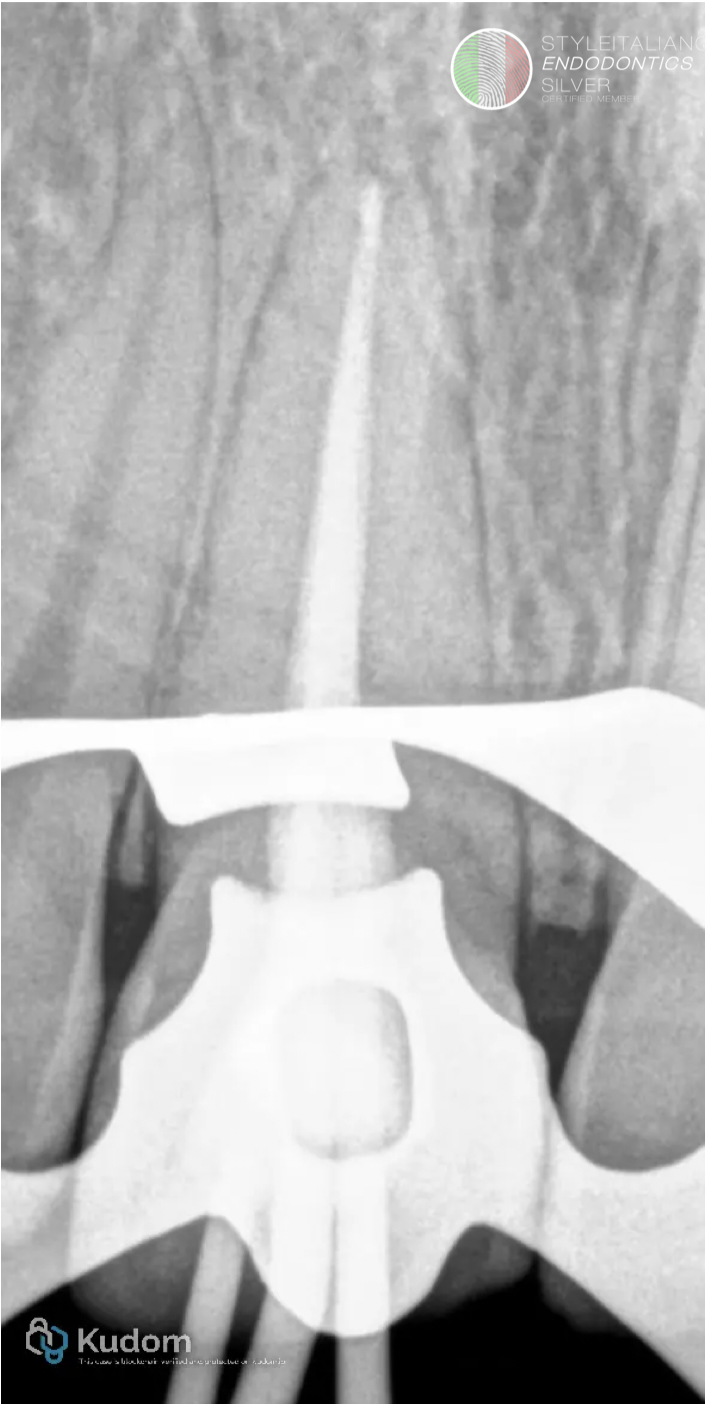

Fig. 5

Apical gauge to the master apical cone confirmed.

Fig. 6

Obturation of the canals by single cone with bioceramic sealer and down back of the cones with obturation pen.